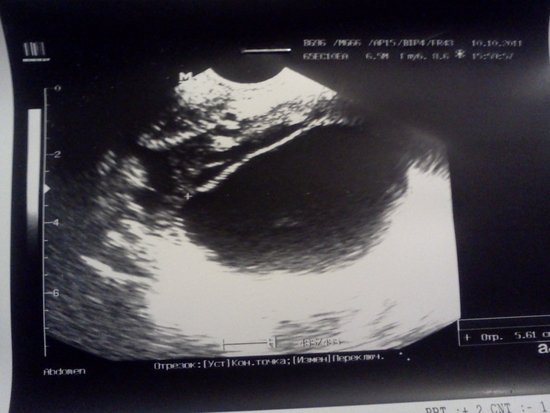

фото УЗИ

Фолликулометрия

Может ли это быть кистой ЖТ

Классические признаки второй фазы!